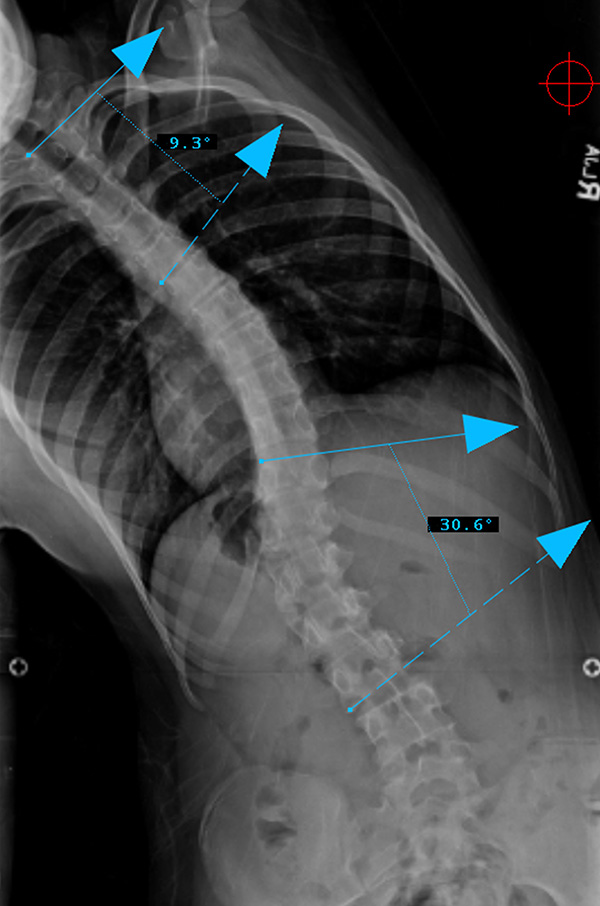

Preop LEFT Bend

Lenke Type V describes a major curve in the thoracolumbar/lumbar region. The apex of the greatest coronal plane deformity is between T12 and L4. The main thoracic curve is non-structural with a side-bending Cobb of less than 25 degrees and a T10-L2 kyphosis of less than 20 degrees. All of these curves have a “C” lumbar spine modifier. The three sagittal modifiers are still applicable. These curves may be treated with either an anterior or posterior spinal fusion. The fusion levels are often the upper and lower end-vertebrae of the coronal plane deformity. For successful selective fusion of the thoracolumbar/lumbar spine the Cobb angle, apical vertebral translation, and apical vertebral rotation ratios (ThL/L:MT) should be greater than 1.25. In addition the MT curve should be flexible without evidence of thoracolumbar junctional kyphosis (T10-L2 > 20 degrees).